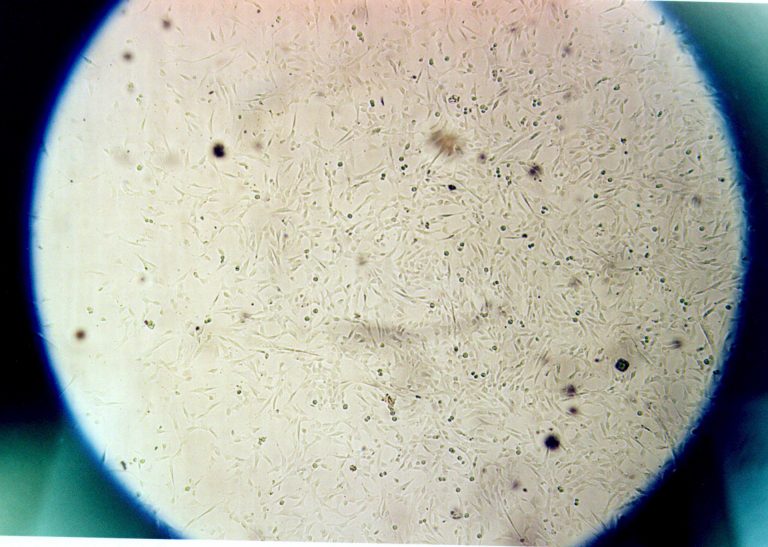

Nombreux tests en laboratoire de différents tissus humains

Prélèvements et analyses afin de contribuer au diagnostic

Examen de chromosomes pour identifier et signaler les anomalies

Programme d'études destiné aux technologistes en laboratoire médical